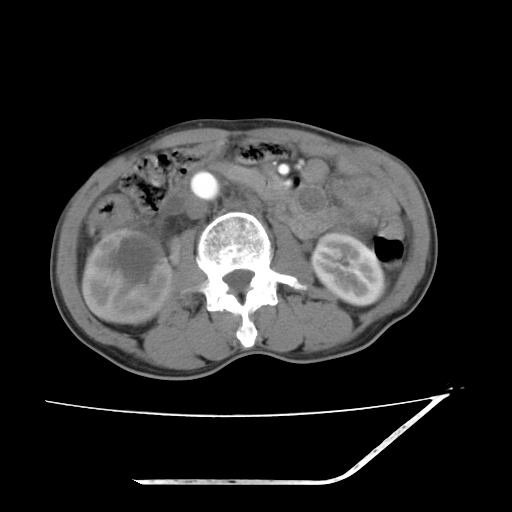

增强

考虑右肾盂癌,肾动脉受侵,右肾功能减退,右肾盂输尿管积水,管壁增厚,考虑种植转移,应该把下面扫完的

支持右侧肾盂癌伴肾静脉瘤栓形成可能性大,右肾结石.肝右叶后段低密度影,不除外转移.

右肾盂旁ca并肾静脉瘤栓形成/肾功能降低。

右肾结石。

右肾盂癌,肾动脉受侵,右肾盂输尿管积水,管壁增厚,考虑种植转移

支持 右侧肾盂癌伴肾静脉瘤栓形成可能性大,右肾结石;肝右叶后段低密度影,不除外转移。

1.右侧肾盂癌伴肾盂积水。

2.肾脏功能减退,原因有:(1)肾动脉受侵。(2)肾静脉受侵(3)肾积水,等。本例,肾动脉显影较好,但受压明显;肾静脉无明显显示,受压或静脉癌栓,下腔静脉腔内未见明显充盈缺损。

3.右侧上段输尿管扩张,原因:(1)积水所致;(2)种植。